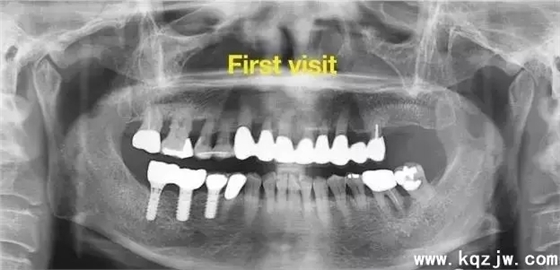

兒童牙外傷是口腔正畸兒童牙科門診的常見病,常發(fā)于上頜前部,而牙齒完全性脫位又是兒童牙外傷中較為嚴(yán)重的一種。我科自1999.9-2004.6共收治16例7-13歲21顆脫位牙,對其進(jìn)行固定正畸技術(shù)即刻再植,術(shù)后定期隨訪1-4年,患牙保持率100%。

本科共收治病例16例,男性15例,女性1例,均為外傷完全性脫位。16例病例中均不含頜骨骨折并輕度牙槽突骨折,其中磕傷13例,他人擊傷3例。21顆外傷脫位牙全部為恒上切牙,其中單牙11例,雙顆牙(連續(xù))6例。

脫位的21顆牙中:19顆無痛、無變色、無松動(dòng)、根尖陰影牙周膜間隙無增大。

2顆有輕度叩痛,根尖有陰影、有輕度變色(后經(jīng)根尖誘導(dǎo)形成術(shù))、叩痛消失、根尖陰影消失,總的患牙保持率100%。